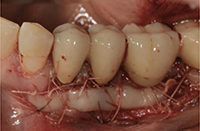

歯肉(歯ぐき)を移植します。

-